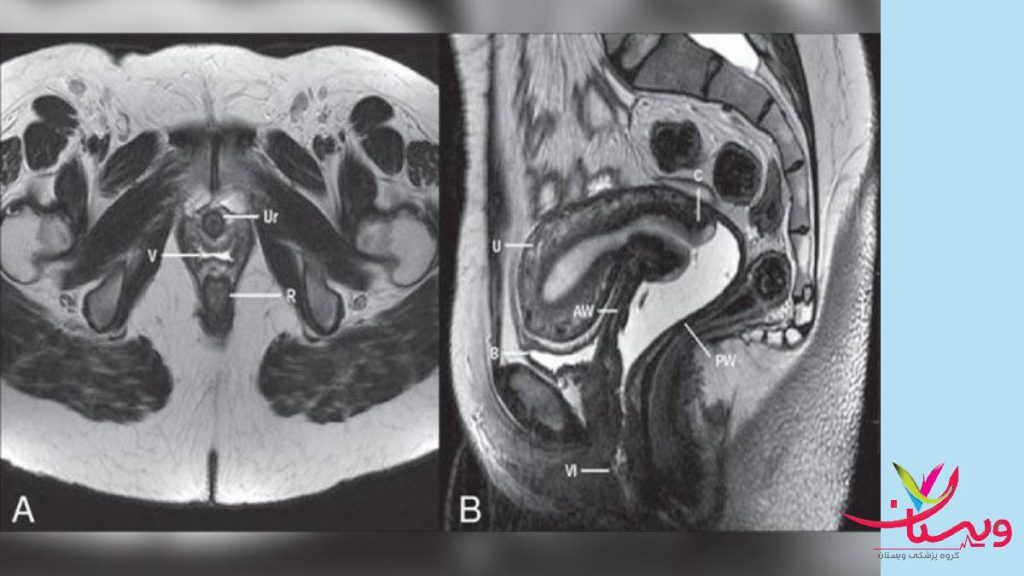

ام آر آی کمر ولگن با تزریق

ام آر آی کمر و لگن با تزریق یکی از روشهای پیشرفته تصویربرداری پزشکی است که برای تشخیص دقیقتر و جزئیتر بیماریها و مشکلات این نواحی از بدن به کار میرود. در این روش، علاوه بر استفاده از میدان مغناطیسی قوی و امواج رادیویی، از یک ماده حاجب خاص نیز استفاده میشود که به صورت وریدی به بدن تزریق میشود. این ماده حاجب، با خاصیتی که دارد، باعث میشود تصاویر به دست آمده از ام آر آی واضحتر و با جزئیات بیشتری باشند.

ام آر آی لگن: این روش برای بررسی ساختارهای داخلی لگن از جمله استخوان ها، عضلات و بافت های نرم استفاده میشود. ام آر آی لگن میتواند به تشخیص مشکلاتی مانند تومورها، التهاب ها و آسیب های ورزشی کمک کند